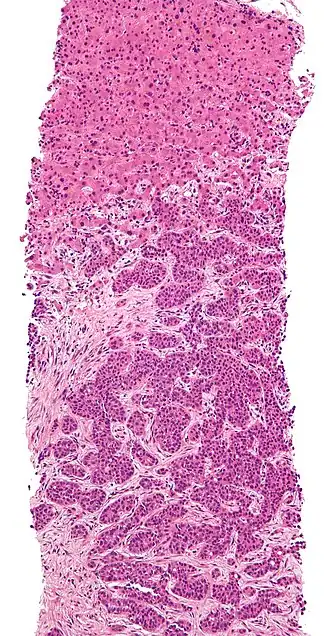

The cells in a metastatic tumor resemble those in the primary tumor. Once the cancerous tissue is examined under a microscope to determine the cell type, a doctor can usually tell whether that type of cell is normally found in the part of the body from which the tissue sample was taken.

For instance, breast cancer cells look the same whether they are found in the breast or have spread to another part of the body. So, if a tissue sample taken from a tumor in the lung contains cells that look like breast cells, the doctor determines that the lung tumor is a secondary tumor. Still, the determination of the primary tumor can often be very difficult, and the pathologist may have to use several adjuvant techniques, such as immunohistochemistry, FISH (fluorescent in situ hybridization), and others. Despite the use of techniques, in some cases the primary tumor remains unidentified.

Metastatic cancers may be found at the same time as the primary tumor, or months or years later. When a second tumor is found in a patient that has been treated for cancer in the past, it is more often a metastasis than another primary tumor.

-

CT image of multiple liver metastases -

CT image of a lung metastasis -

Metastatic cancer in the lungs -

Metastases from the lungs to the brain -